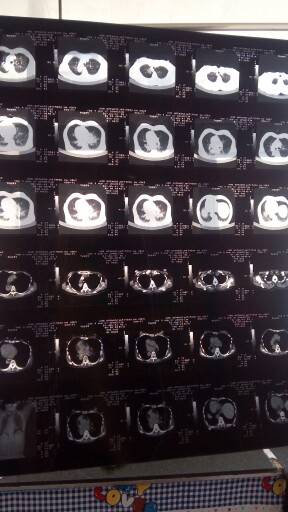

妈妈肺部和脑部肿瘤消失了